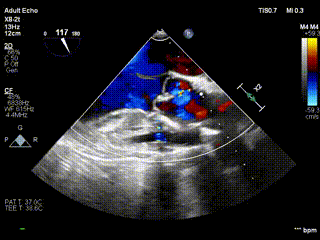

视频3:病例2术前心超提示大量主动脉瓣反流

视频4:病例2术后无反流